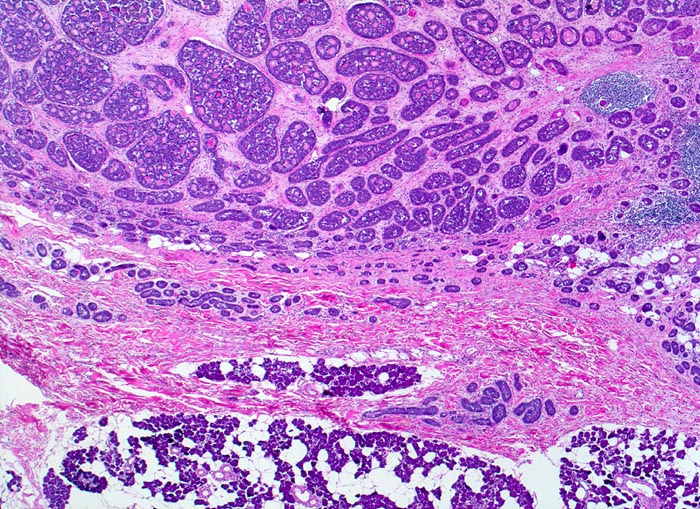

adenoidzystisches Karzinom der Glandula Parotis

Unten im Bild eine rein seröse von Fettgewebe durchsetzte Speicheldrüse. Oben im Bild ein unscharf begrenzter aus kribriformen, tubulären und soliden Zellformationen aufgebauter Tumor.

Schmerzhafter, rasch wachsender unscharf begrenzter Tumor in der Glandula Parotis.